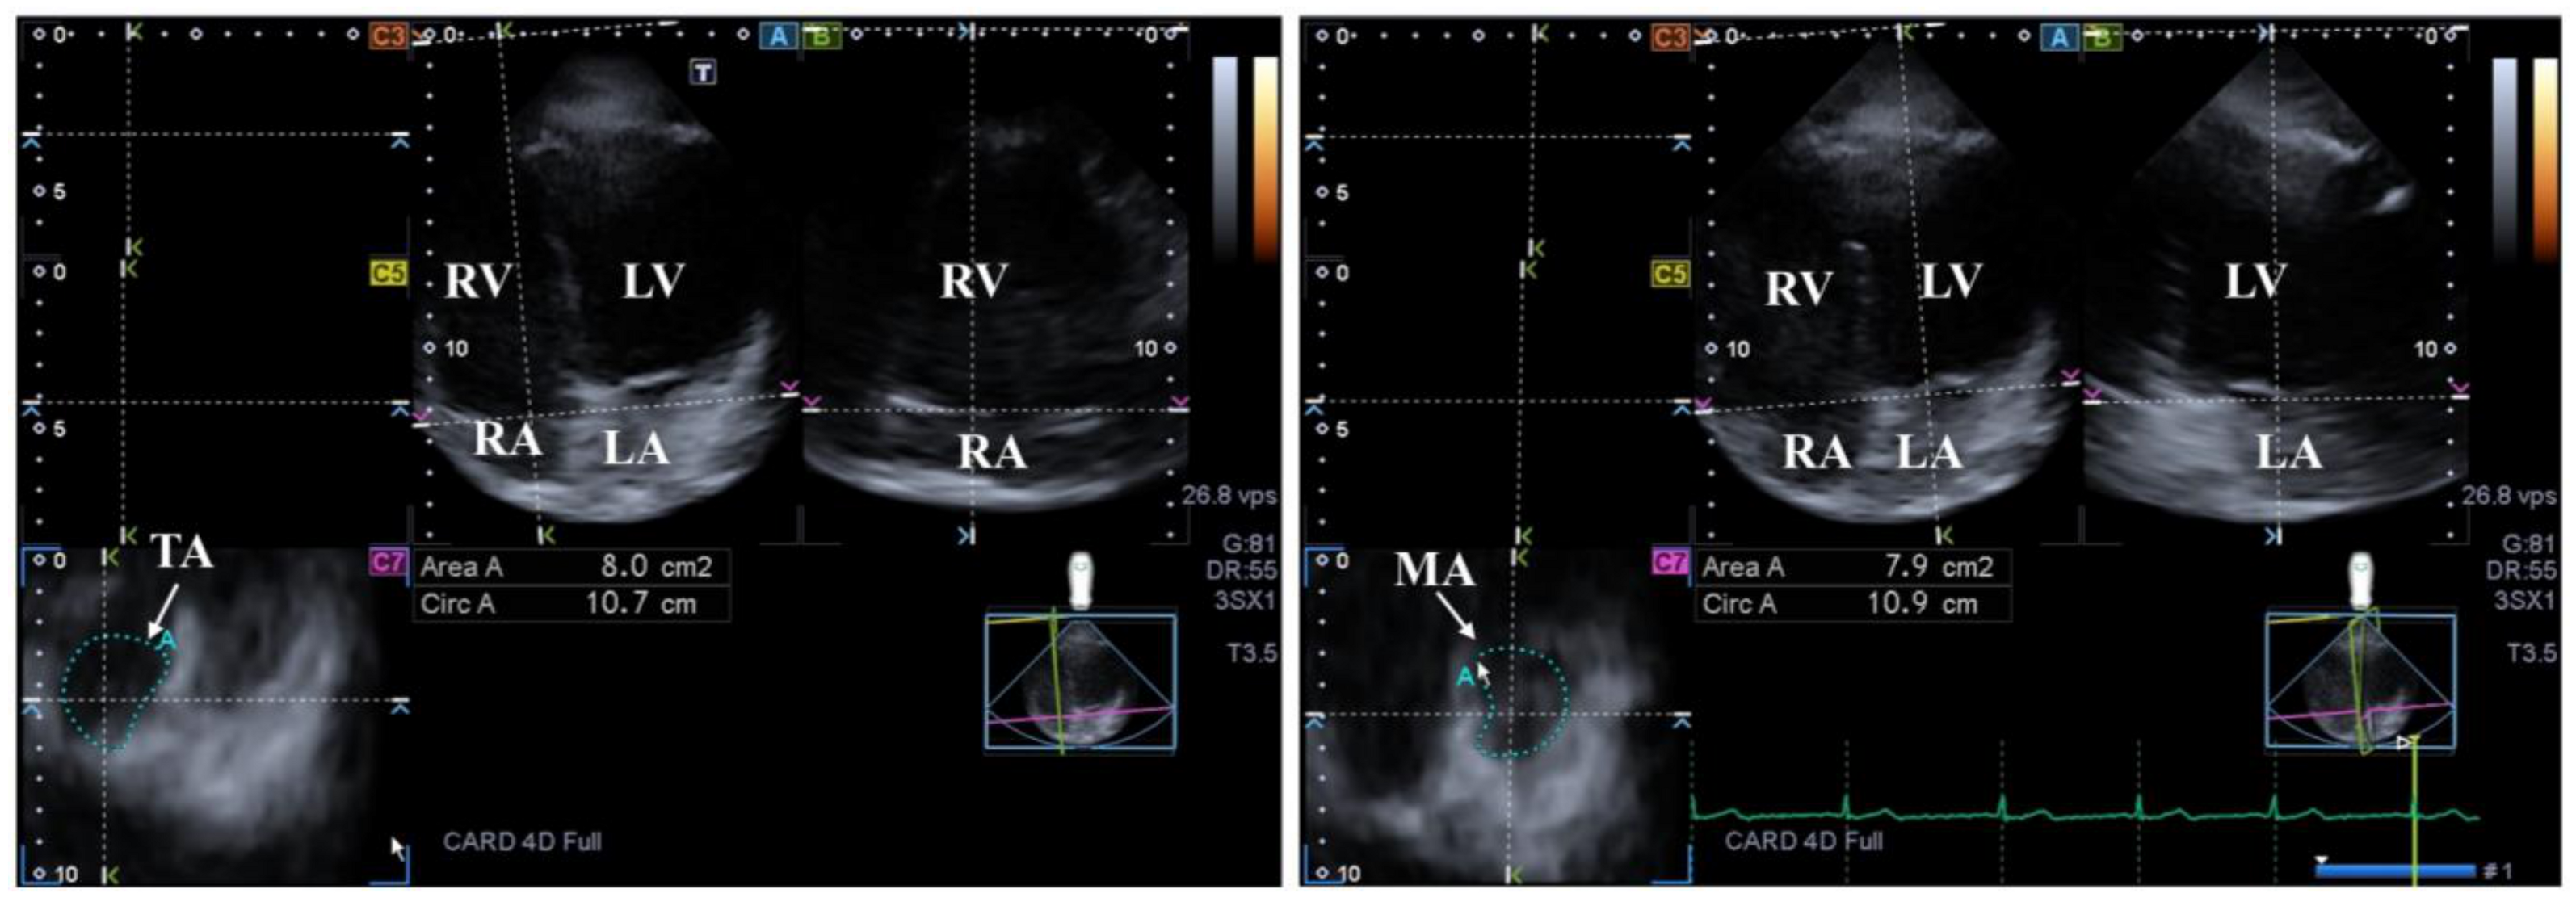

The MV has several components: two leaflets, a subvalvular apparatus consisting of chordae tendinae and papillary muscles and a saddle-shaped annulus (MA) that has a dynamic motion respecting the heart cycle. The MV opens/closes during diastole/systole with one-way flow of blood from the LA into the LV in normal healthy circumstances. Adjacent regions of these heart chambers have a significant role in the contraction of MV [16,59,60] (Figure 3).

Figure 3.

Examination of the tricuspid (TA) and mitral (MA) annuli by three-dimensional (3D) echocardiography (left panel and right panel, respectively). (A) Apical 4-chamber and (B) two-chamber longitudinal views help visualization of valvular annuli on (C7) cross-sectional view. TA and MA planes are marked by a white arrow. TA and MA can be easily detected alongside the heart chambers including the left ventricle (LV) and atrium (LA) and the right ventricle (RV) and atrium (RA).

4.3.1. Under Healthy Circumstances

The tricuspid valve has several components: three leaflets, a subvalvular apparatus consisting of chordae tendinae and papillary muscles and an asymmetrical, saddle-shaped, ellipsoid annulus (TA) that has a dynamic motion respecting the heart cycle. The tricuspid valve opens/closes during diastole/systole with a one-way flow of blood from the RA into the RV in normal healthy circumstances [107] (Figure 3).